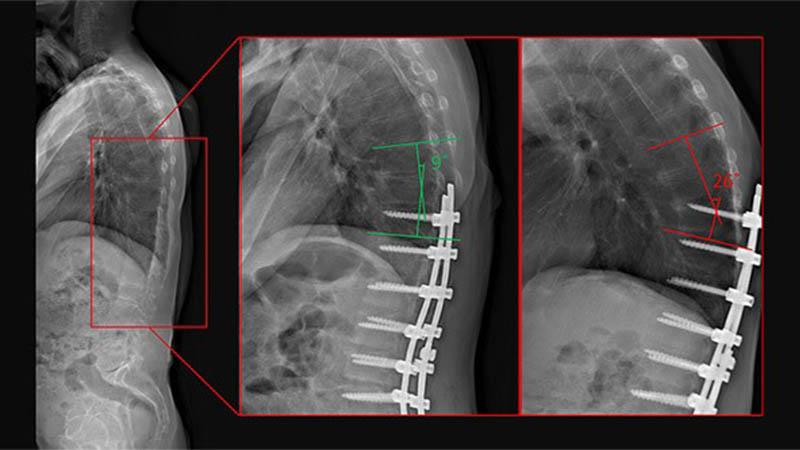

Radiology images of a patient with PJK. (Left) baseline (no hardware), (middle) immediate postoperative image (no PJK), and (right) 2.5 years follow-up image (PJK)

Identifying Novel Metrics for Risk of Proximal Junctional Kyphosis

Researchers from Och Spine at NewYork-Presbyterian built a machine learning algorithm to identify novel metrics associated with proximal junctional kyphosis (PJK) – a common postoperative complication following spinal deformity surgery – in addition to recording their strength relative to established risk factors. The orthopedic surgeons are planning to use these learnings to develop an app that can help educate patients as to their risk of PJK, show how changes preoperatively can help influence or prevent the common complication, and assist surgeons in clinical decision-making.